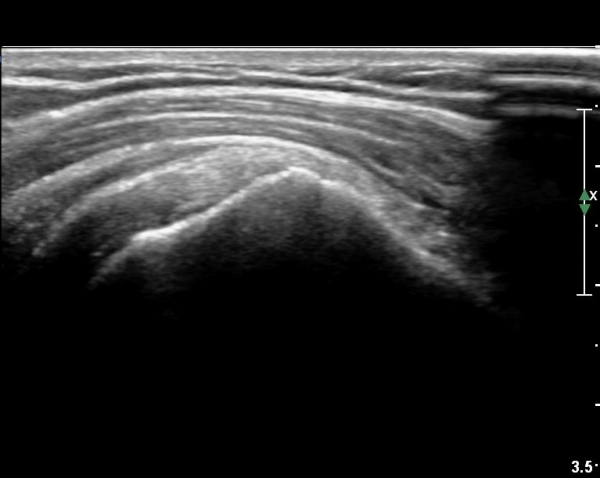

±Ø»ó°Ç Á¶´ã¸é°Ë»ç¿¡¼­ ±Ø»ó°ÇÀÇ ÅðÇ༺º¯È­È­ ºÎºÐÀûÀÎ ÆÄ¿­ÀÌ  °üÂûµÇ¸é ´ë°áÀýÀº

ºñÈĵǾî ÀÖ´Ù(»çÁø 6, 7, 8).

ȸÀü±Ù°³ Ⱦ´Ü¸é°Ë»ç¿¡¼­ ȸÀü±Ù°³ ³»Ãø Áï ±Ø»ó°Ç ³»ÃøÀÇ Àú¿¡ÄÚ ºÎÁ¾ÀÌ °üÂûµÈ´Ù(»çÁø 10).